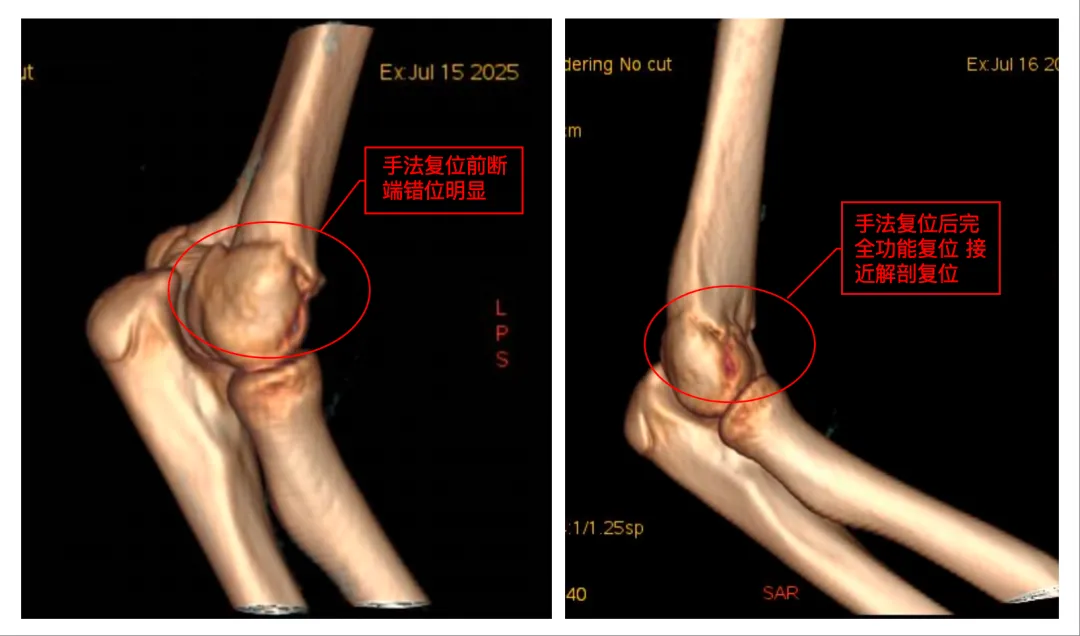

急匆匆询问了一下本地人,她们来到威海卫人民医院手足外科就诊。拍片、诊断、复位、固定,整个迅速又专业的诊疗过程让李妈妈深感意外,主诊医生的精湛操作让孩子免于手术创伤,更令李女士动容的是无处不在的人文关怀医护人员耐心解答、细致指导,导医护士主动帮忙……最让李妈妈感动的是,接诊医生得知她们是外地游客,特意把复查时间安排得相对灵活。